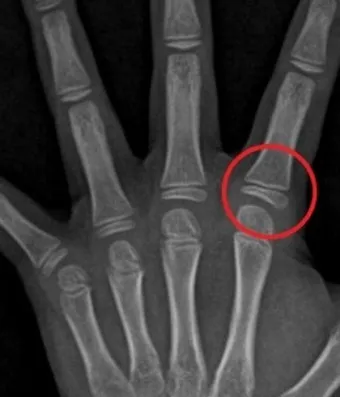

성장판은 하나의 문이 갑자기 '딱' 닫히는 것이 아닙니다. 손가락, 발가락, 손목, 발목, 골반, 척추 순으로 뼈 끝 쪽의 연골이 굳어져 가는 과정은 꽤 오랜 시간이 걸려요. 성장판의 닫히는 시기는 개인차가 매우 크답니다.

일반적으로 여성은 14-15세, 남성은 16-17세에 성장판이 닫히기 시작하지만, 완전히 닫히는 것은 만 19-20세경이에요. 하지만 여기서 중요한 건, 성장판 검사에서 '닫혔다'고 나와도 검사 오차가 있을 수 있고, 미세하게 남아있는 성장판으로 인한 성장 가능성이 남아있다는 점입니다.